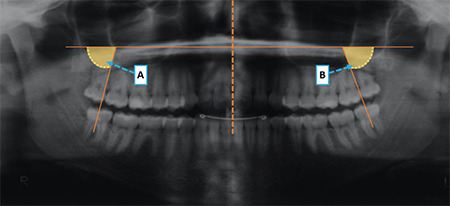

Methods: The sample comprised 93 patients divided into four groups: Group 1, Class I malocclusion treated with first premolar extractions; Group 2, Class I malocclusion treated without extractions; Group 3, Class II malocclusion treated with first premolar extractions; and Group 4, Class II malocclusion treated without extractions. Panoramic radiographs were used to evaluate the third molar mesiodistal angulations at T1 (pretreatment), T2 (posttreatment), and T3 (long-term posttreatment). Third molar eruption status was assessed in dental casts. Intergroup angulations and eruption status comparisons were performed using one-way analysis of variance (ANOVA), followed by Tukey's test and Kruskal-Wallis test, respectively.